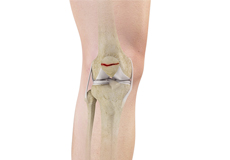

Ligaments of the Knee

Ligaments are tough bands of tissue that connect one bone to another bone. The ligaments of the knee stabilize the knee joint. There are two important groups of ligaments that hold the bones of the knee joint together, collateral and cruciate ligaments.

Collateral ligaments are present on either side of the knee. They prevent the knee from moving too far during side to side motion. The collateral ligament on the inside is called the medial collateral ligament (MCL) and the collateral ligament on the outside is called the lateral collateral ligament (LCL).

Cruciate ligaments, present inside the knee joint, control the back-and-forth motion of the knee. The cruciate ligament in the front of the knee is called anterior cruciate ligament (ACL) and the cruciate ligament in the back of the knee is called posterior cruciate ligament (PCL).